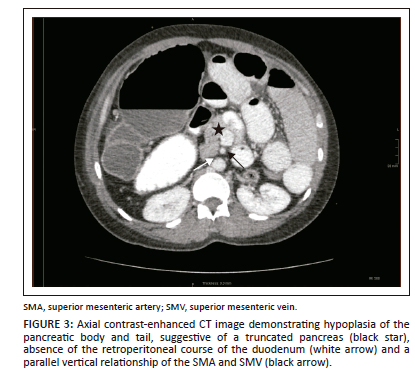

A CT of the abdomen revealed right-sided polysplenia (Figure 1) with a dominant parent spleen, a left-sided liver, extending across the midline, and a right-sided stomach (Figure 2). The superior mesenteric artery and vein were parallel to one another (Figure 3). The duodenum coursed anterior to the portosplenic vein with the duodenojejunal junction located to the left of the left-sided vertebral body pedicle but inferior to the level of the duodenal bulb, in keeping with some degree of malrotation. The jejunal loops were located in the left side of the abdomen. There was twisting of the mesentery in the right lower quadrant (Figure 4) with small bowel dilatation and massive dilatation of the caecum and proximal ascending colon (Figure 5). The transition point was within the proximal to mid ascending colon, with collapse of the large bowel distal to this point. There was also dilatation of the small bowel, most likely due to an incompetent ileocecal valve. A small amount of free fluid was noted in the right paracolic gutter and the Pouch of Douglas with multiple mesenteric lymph nodes in the right iliac fossa. Additionally, there was absence of the uncinate process of the pancreas suggestive of a truncated pancreas (Figure 3).